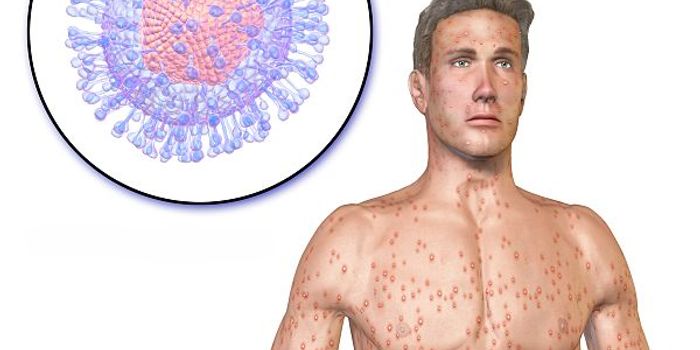

NOV 20, 2022ImmunologyGerman scientists provided a case study of a 51-year-old patient that highlighted one of the first symptoms a monkeypox- ...